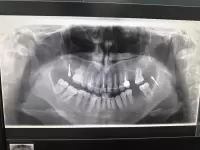

Мой случай был сложным: более 6 лет безуспешного лечения, постоянные поломки ретейнера и нежелание предыдущего врача продолжать работу, что привело к образованию щелей и расхождению зубов. Родион Дамирович не только взялся за исправление ситуации, но и сделал это блестяще. За полгода наблюдения за его работой я ни разу не усомнилась в его решениях — его серьезный, уверенный и непоколебимый подход внушает полное доверие.

Ему удалось за несколько приемов исправить прикус и вернуть зубы в корректное положение, что я считаю настоящим профессиональным подвигом. Сейчас мы успешно переходим к этапу протезирования — установке временных коронок.

Проходил здесь ортодоническое лечение, более года носил брекеты, исправил зубной ряд, в данный момент установлены ретейнеры, но уже результат заметно, в положительную сторону. Врач всегда на связи, готов ответить на любые вопросы, спасибо за проделанную работу, хорошие стоматологи и хорошее оборудование для диагностики.

На фото: наши бразильские пациенты - футболисты Даниель Корвалио и Вагнер (Лав).